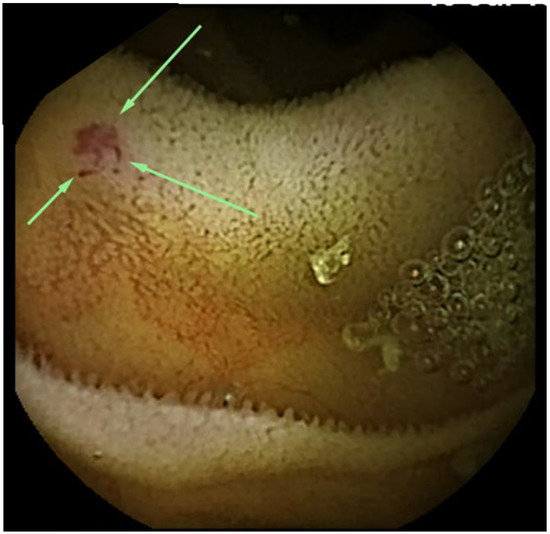

Contribution of Capsule Endoscopy Early in a Bleeding Episode to Treatment of Small Bowel Angioectasia: A Case Report

2. Case Presentation